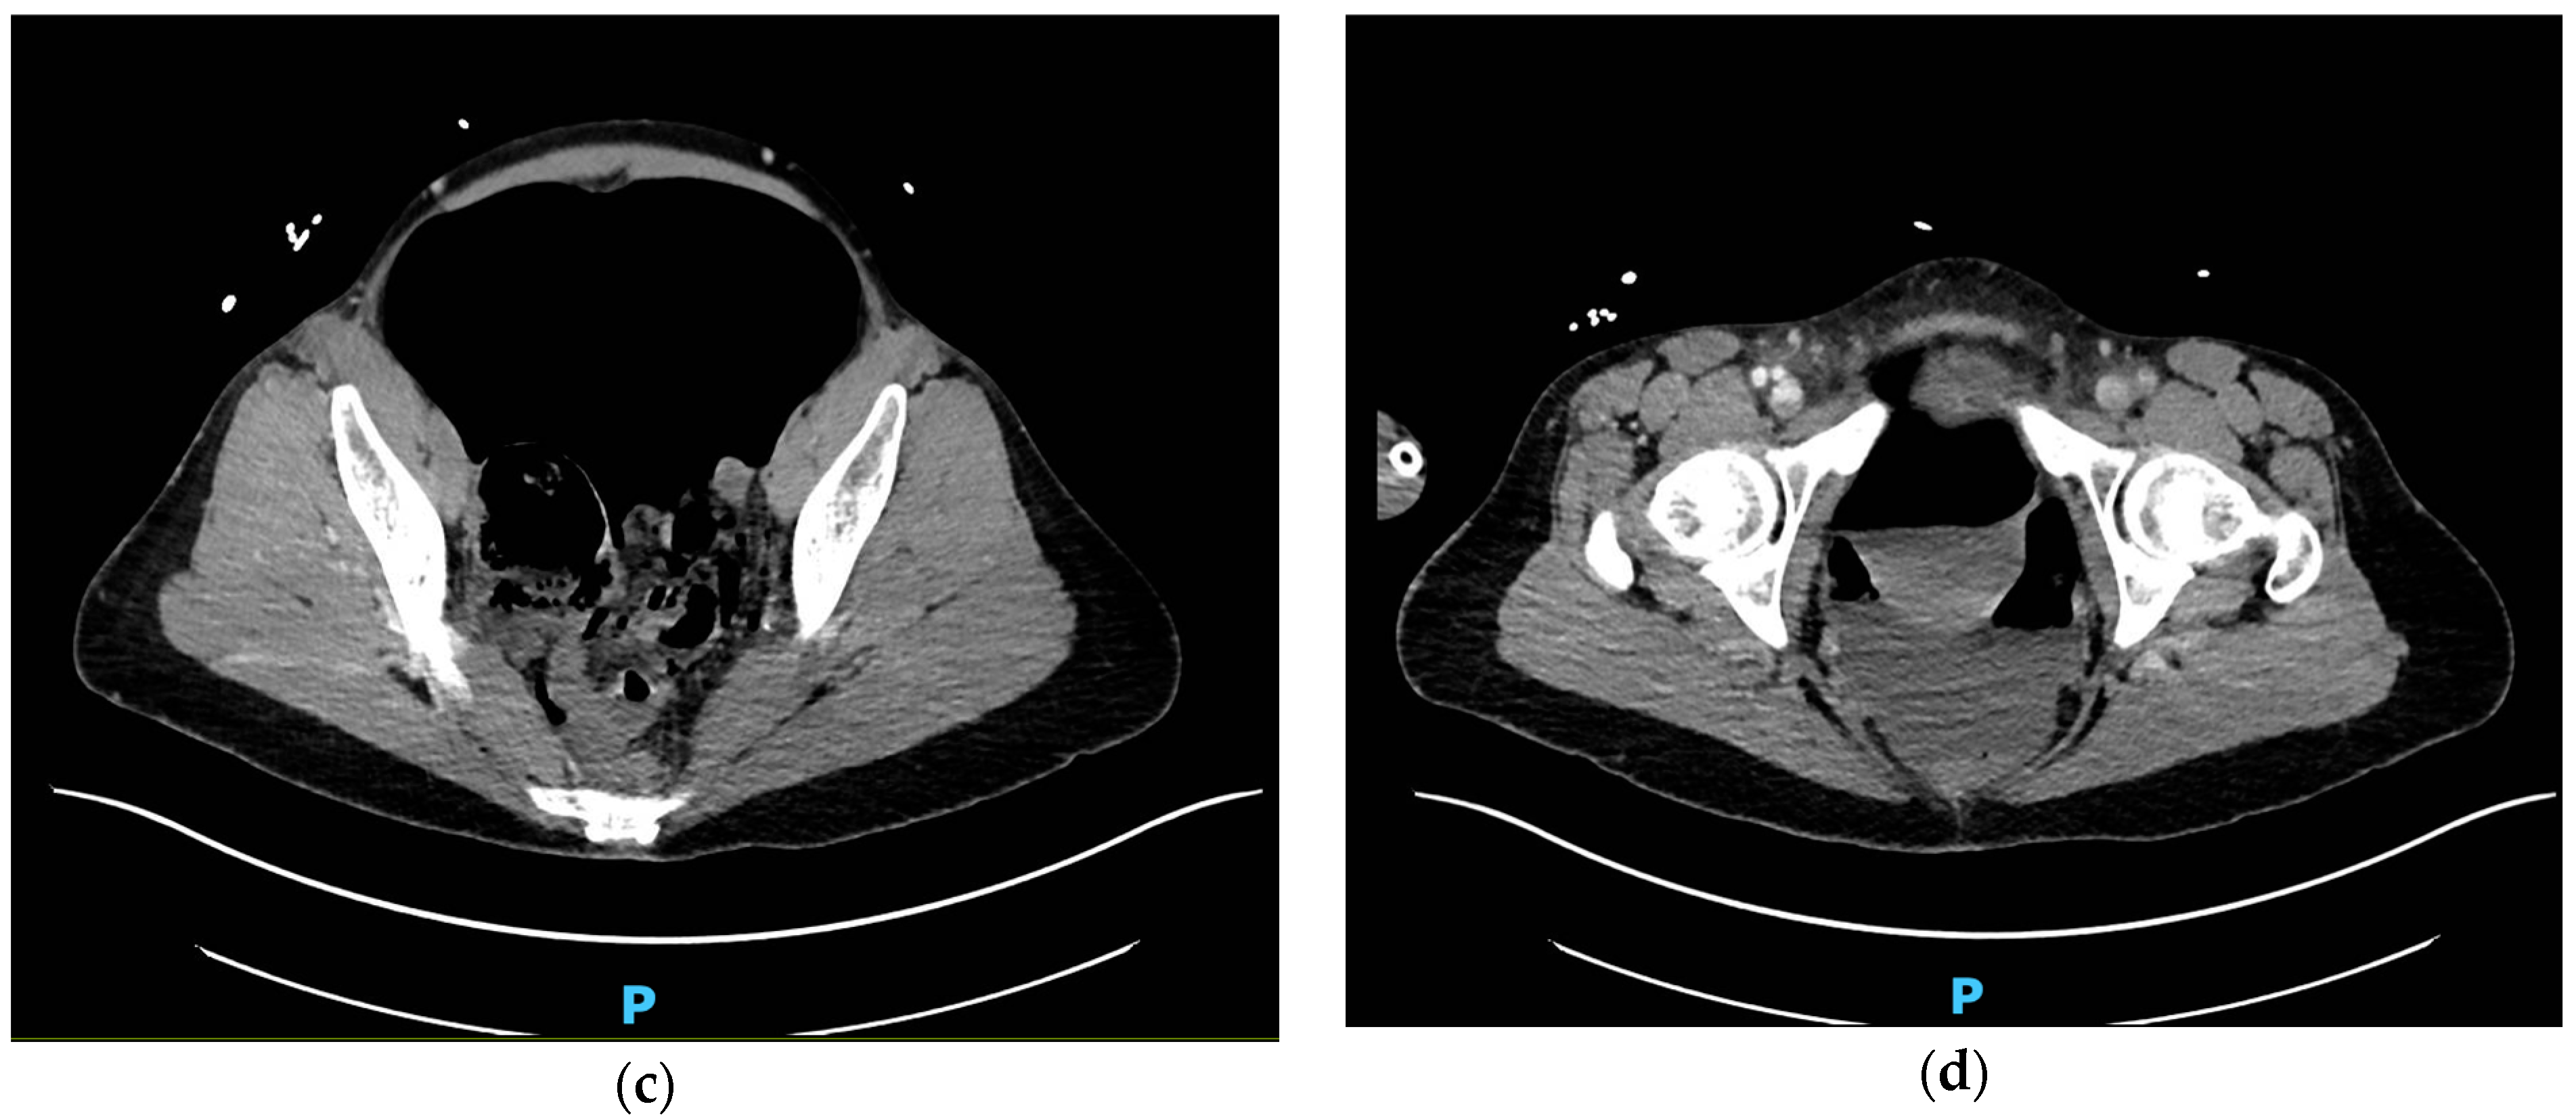

Gastric Perforation from Bag-Valve-Mask Ventilation Resulting in Tension Pneumoperitoneum and Arterial Insufficiency

2. Case Presentation